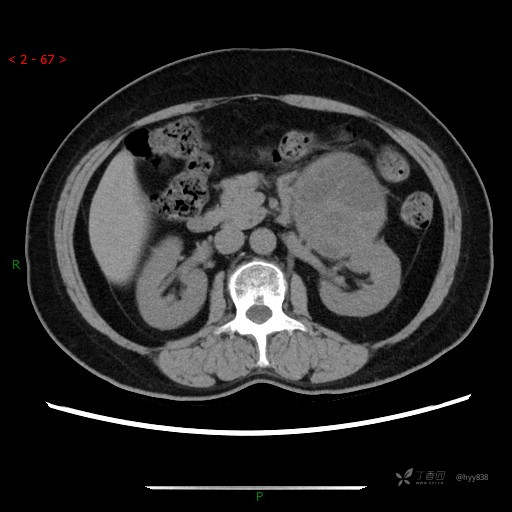

中腹部CT平扫